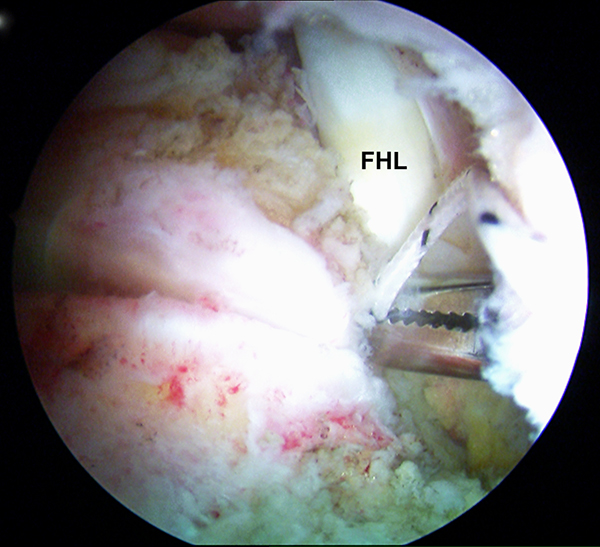

Einführen des 4,0 mm Arthroskops über den posterolateralen Zugang und des Shavers über das posteromediale Portal. Es wird zunächst ein Weichteildebridement im Kagerschen Raum durchgeführt, bis die Flexor hallucis longus-Sehne (FHL) identifiziert werden kann (siehe auch Kapitel „Dorsale Arthroskopie des oberen und unteren Sprunggelenks“, Abbildungen 5-10).

Zum Lesen der Bildbeschreibung und zur Vollansicht bitte das Bild anklicken. Foto: M. Galla.

Abbildungen 5-8, Video 2

Anschließend wird die FHL-Sehne angeschlungen. Hierzu wird die Fadenschlaufe über das posteromediale Portal mit einer Fadenzange oder einem gebogenen Klemmchen um die FHL-Sehne geführt und anschließend wieder aus dem Portal herausgezogen. Nach Durchfädeln der freien Fadenenden durch die Schlaufe wird die Schlinge festangezogen. Die Technik wird in Video 2 demonstriert.

Zur Vollansicht bitte die Bilder anklicken. Fotos: M. Galla.